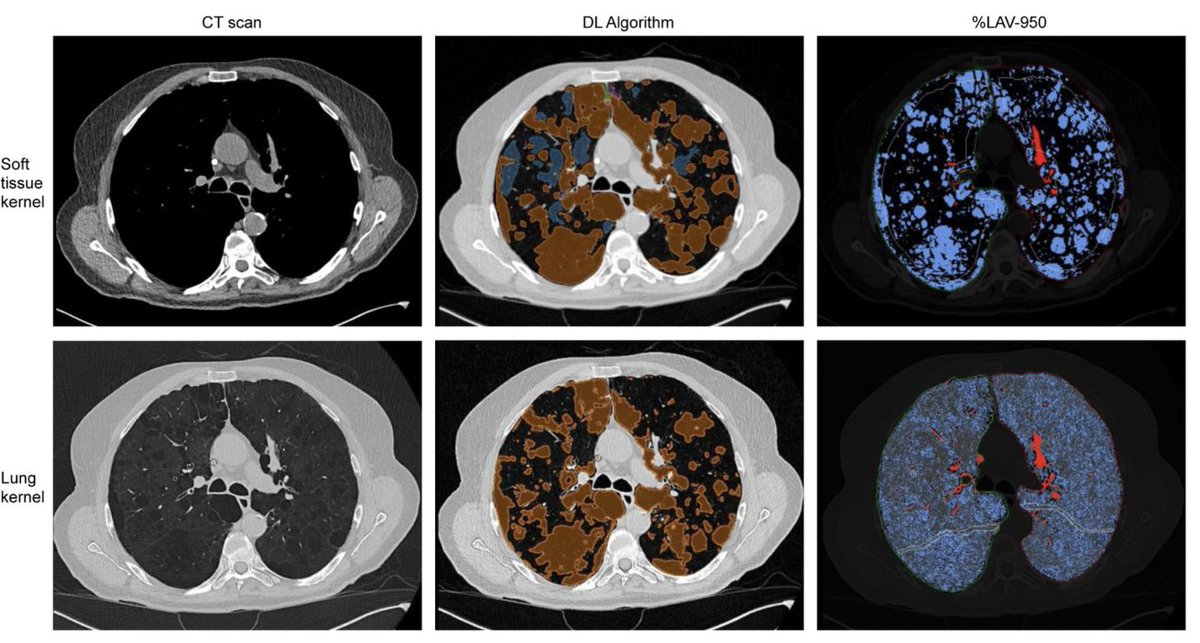

🫁 Research from Zurich compared two methods for measuring #emphysema in CT scans of #COPD patients: traditional HU vs. @contextflow_rad's #deeplearning method